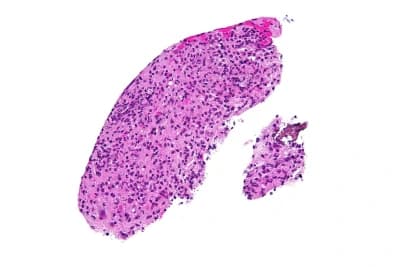

Representation of the Toxoplasma gondii parasite responsible for toxoplasmosis

Toxoplasmosis is an infectious disease caused by a microscopic parasite called Toxoplasma gondii. This parasite is an obligate intracellular protozoan: it needs to penetrate the cells of a living organism to develop and reproduce.